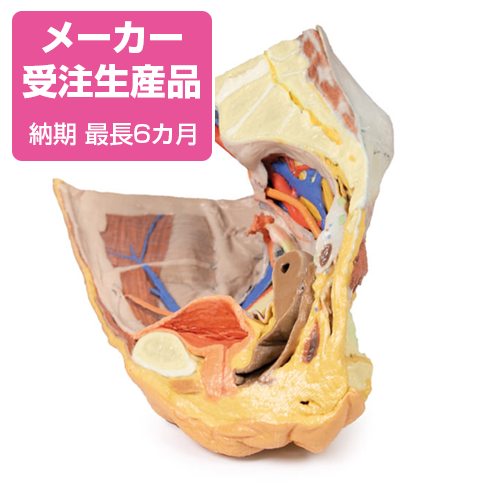

津野田 雅敏 | 放射線科 | 診療科・部門 | 心臓病センター榊原病院, 予約販売】女性の右骨盤の表層と深部 - 京都科学オンラインショップ,

予約販売】女性の右骨盤の表層と深部 - 京都科学オンラインショップ, 第52回日本核医学会学術総会/第32回日本核医学技術学会総会学術,